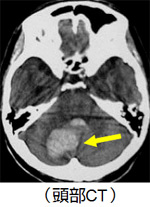

診断は頭部CTを施行することで簡単に診断することが可能です。下の頭部CTで黄色い矢印の白くうつる部分が脳出血になります。

小脳というバランス感覚を養う部分に出血していますので診断は小脳出血です。ここに出血すると力はしっかりあるのに立てなかったり、吐き気が強く嘔吐したり、回転性のめまいが頻発したりします。